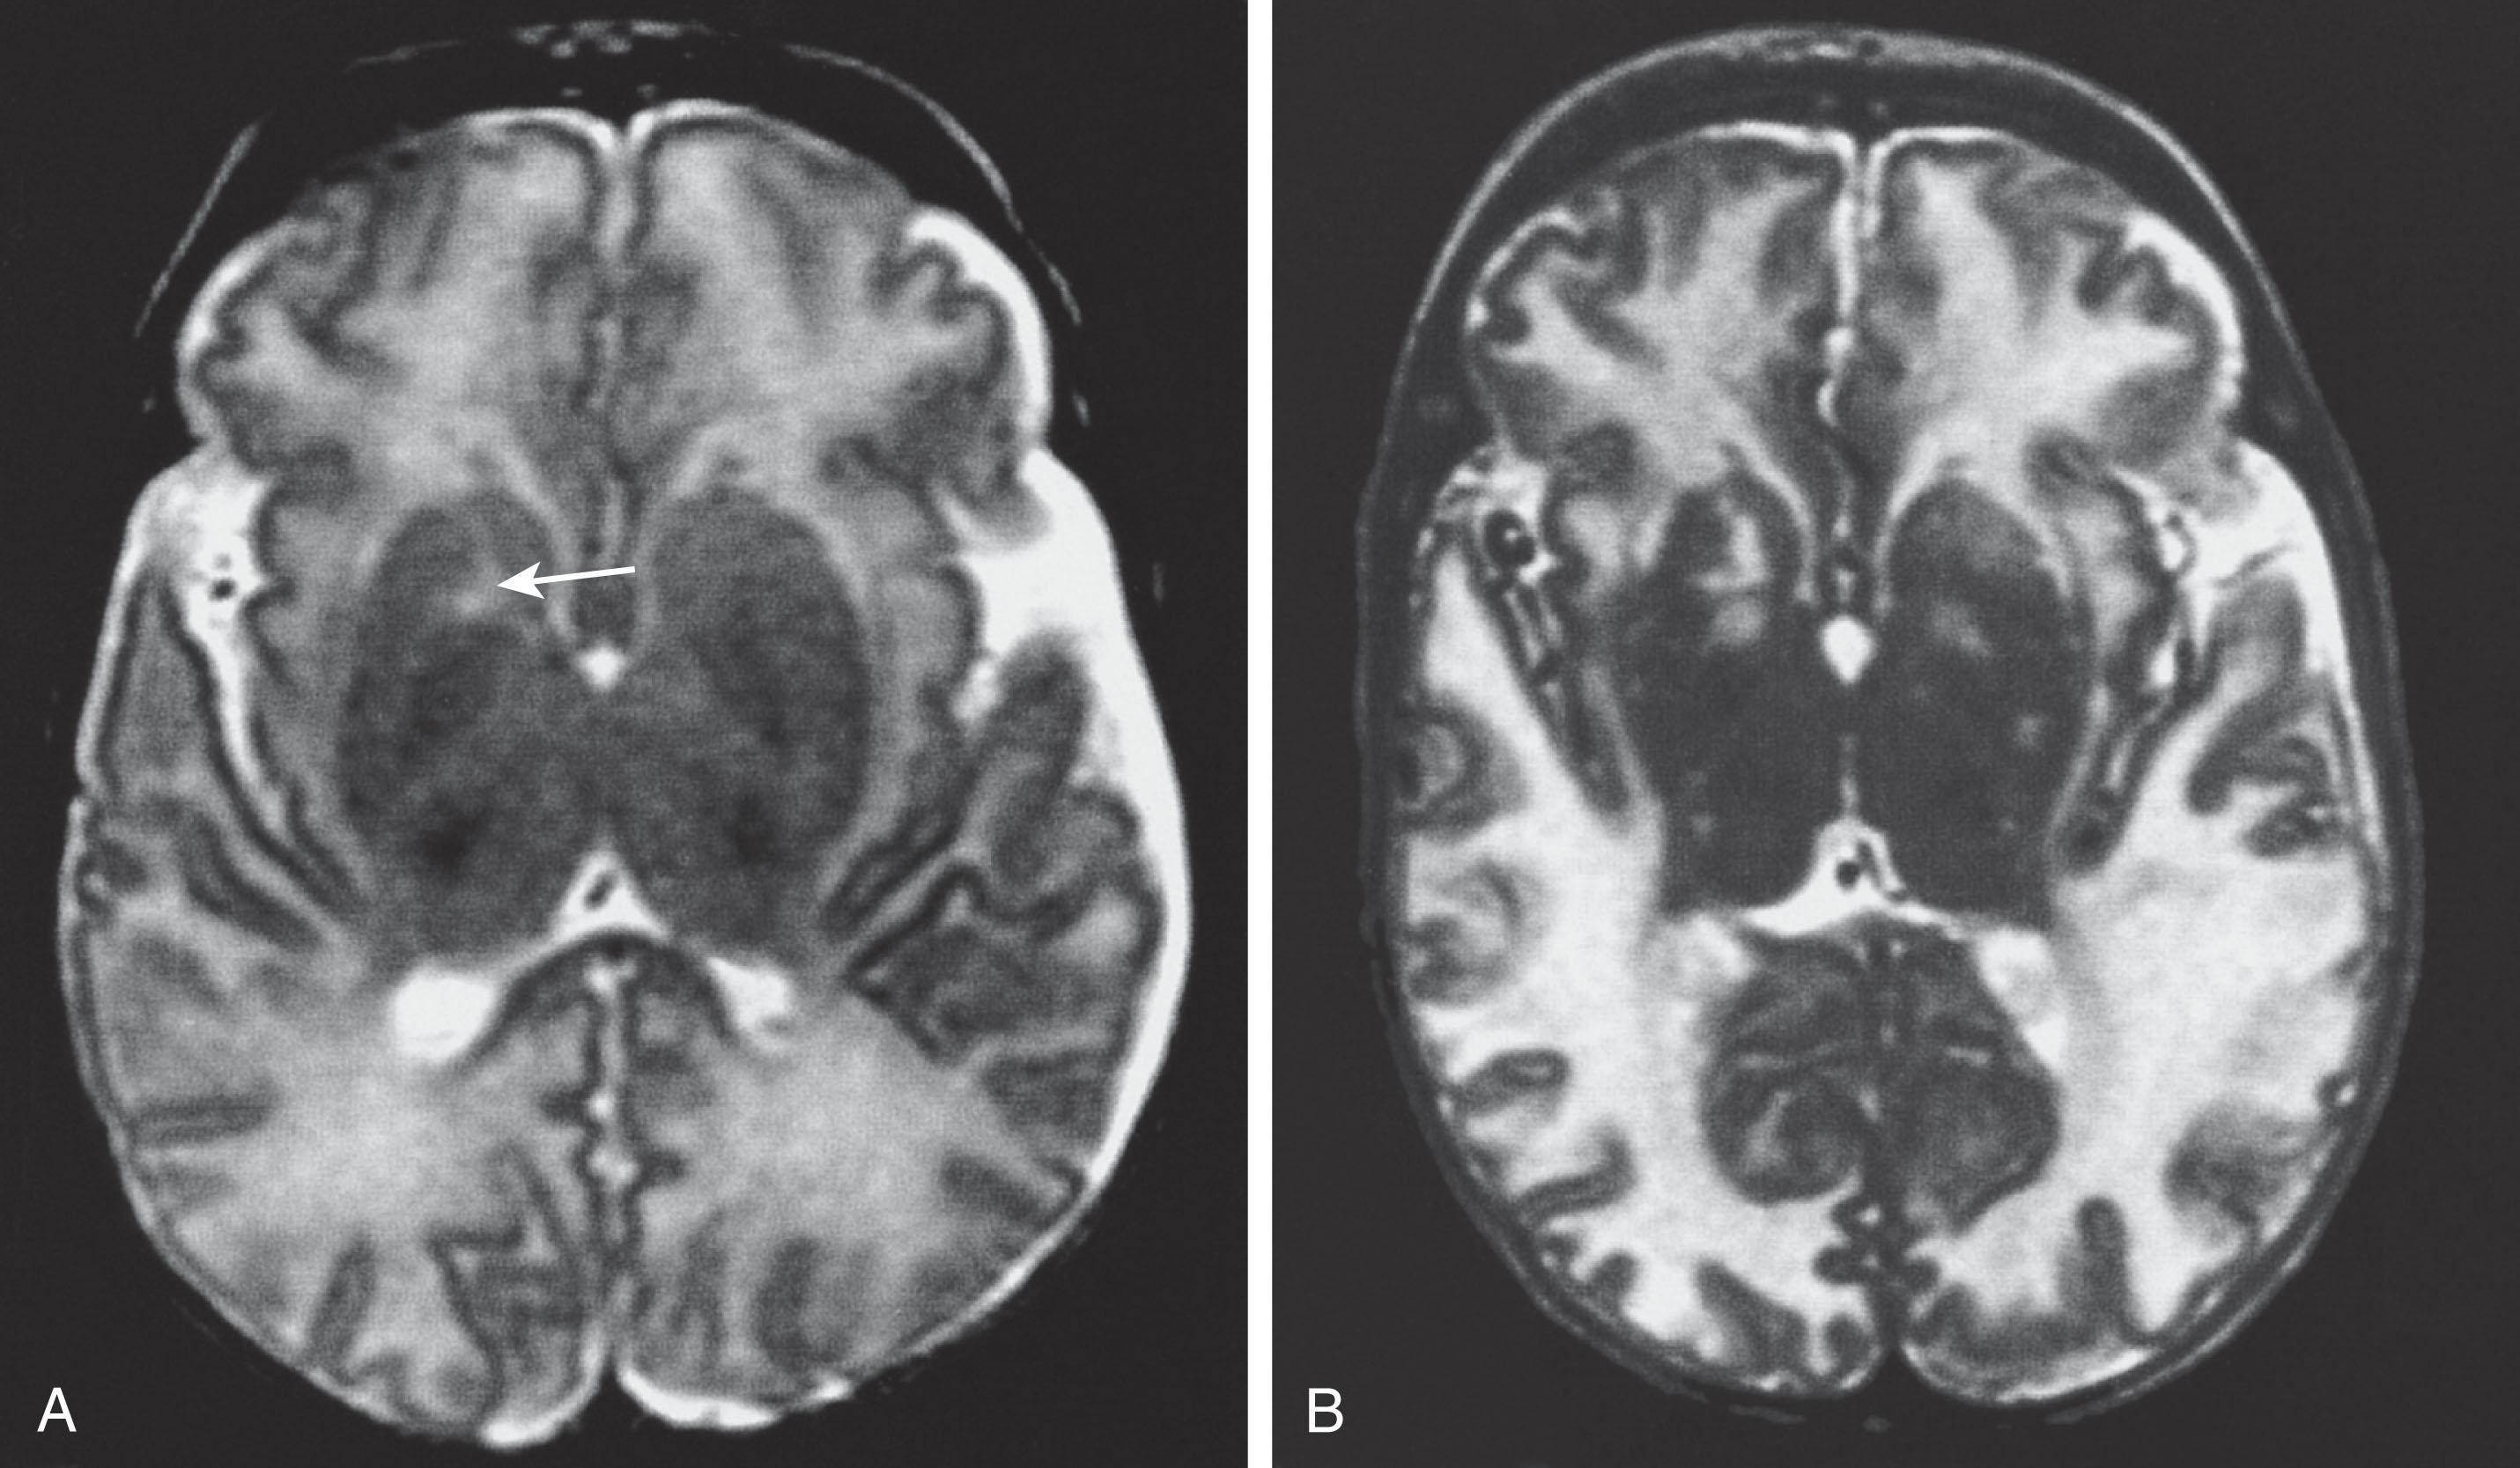

The term Alpers disease , inappropriately applied in the past to a heterogeneous group of disorders, refers to those relatively uncommon examples, usually familial and consistent with autosomal recessive inheritance, of a progressive degenerative disease of gray matter without neuronal storage or other pathognomonic cytological features and with subsequent hepatic disease. Affected infants exhibit the clinical hallmarks of gray matter disease, seizures, and myoclonus (often stimulus sensitive) in the first weeks and months of life (see Table 33.2 ). Hypotonia and vomiting are also prominent features. In one series, 4 of 26 infants had clear onset within the first 2 months of life. Hepatic disease becomes apparent usually after 9 months of age (mean age, 35 months), but a more frequent assessment of serum transaminase levels before the appearance of hepatomegaly demonstrates hepatic dysfunction earlier. Most infants die by 3 years of age. MRI shows extensive cerebral atrophy ( Fig. 33.6 ).

Fig. 33.6, Alpers disease: MRI. T1-weighted image at age of 4 days with no cortical atrophy or abnormal findings (A). Same patient (B) imaged 3 months later. T2-weighted image shows extensive brain atrophy with widened sulci ( black arrows ) and compensatory fluid accumulation around the cerebrum ( white, thick arrows ). Note increased signal in the putamen ( white, thin arrow ).